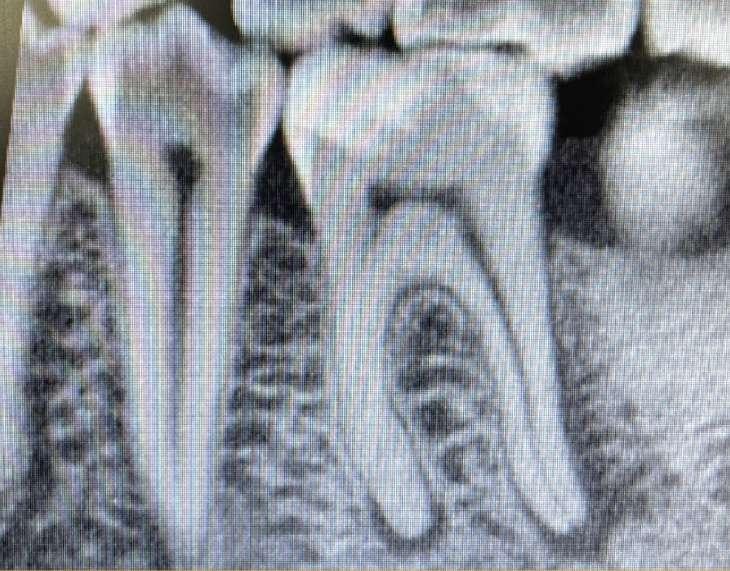

Wenn man sich dieses präoperative Röntgenbild ansieht, sind zwei Hinweise zu diesem endodontischen Fall zu erkennen (Abb. 1): Obliteration der Pulpakammer und enge Kanäle Ungewöhnliche Anatomie der distalen Wurzel

FALLBERICHT: Abb.1 Abb.2